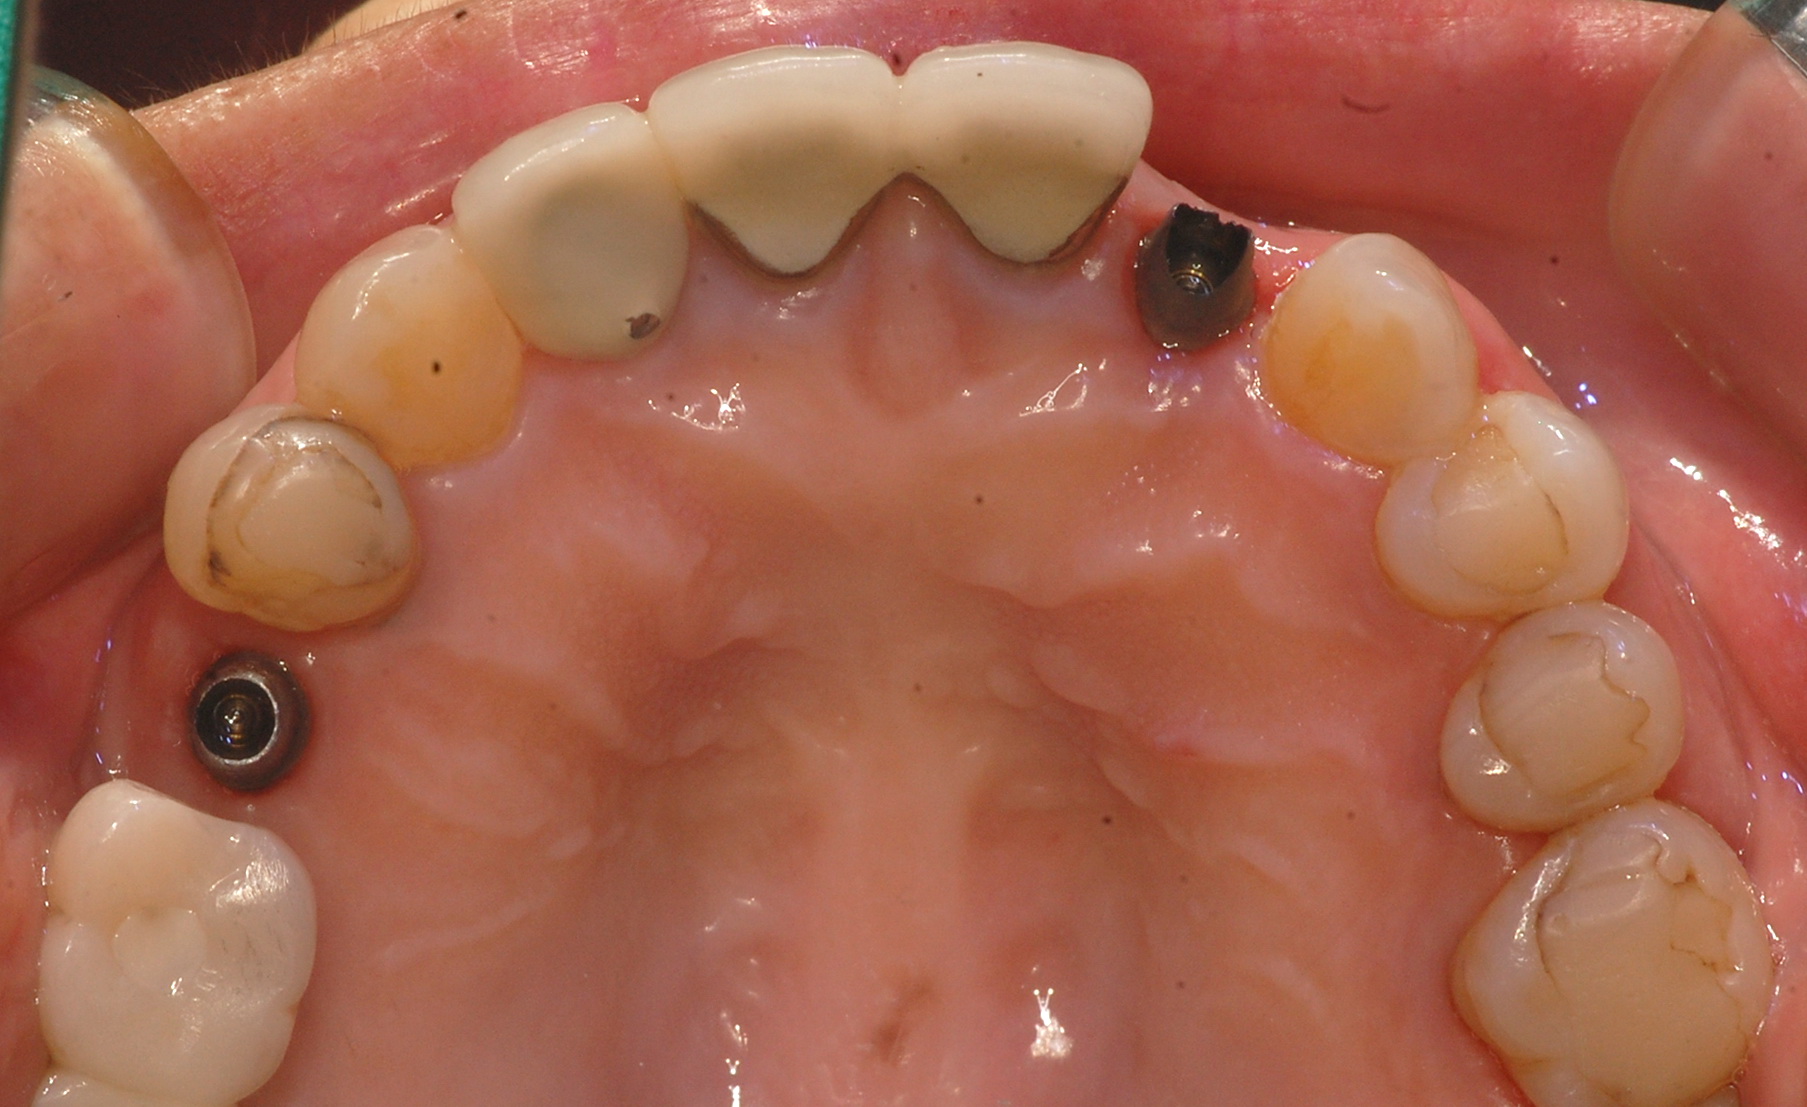

[임플란트] 제목 : 임플란트 PFM 보철

임플란트 PFM 보철